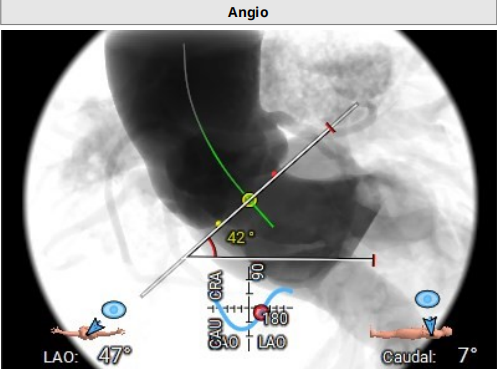

该患者主动脉弓降结合部迂曲,成角极大达到84°,此外合并胸骨畸形、脊柱侧弯,CT测算的共平面工作体位难以实现,计划通过术中垫肩、减少左前斜角度,方便操作。考虑到患者瓣环周长21.9mm,拟使用25mm J-Valve。

猪尾放置于无冠窦行根部造影,通过垫患者左肩、最终左前斜12°,实现三窦切线位: